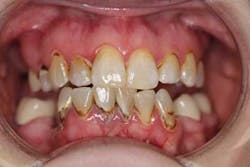

After a complete assessment, it was apparent that Sara’s options were limited with her existing dentition. The caries present were large and apple-cored around the teeth, making the long-term restorative prognosis questionable or guarded at best (figures 2-5). Several key teeth for partial abutments were either missing or grossly carious.